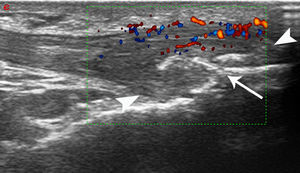

The PDUS appearance of dysmetabolic enthesopathies comprises all pathologic changes typical of enthesitis (thickening, hypoecogenicity, neovascularization), even if these abnormalities often spread from the enthesis toward the mid-portion of tendon, with a peculiar gross appearance of enthesophytes (Fig. 1).

Patellar tendon enthesopathic changes in patient with metabolic syndrome. Anterior longitudinal scan over the distal enthesis of patellar tendon, linear 6–18MHz probe. The distal enthesis of the patellar tendon (between arrowheads) is markedly thickened and hypoechoic, with gross enthesophytosis (arrow). Power Doppler analysis (within the color box) shows abundant neovascularisation in the distal third of the tendon. All the abnormalities spread beyond the real enthesis toward the body of the tendon.